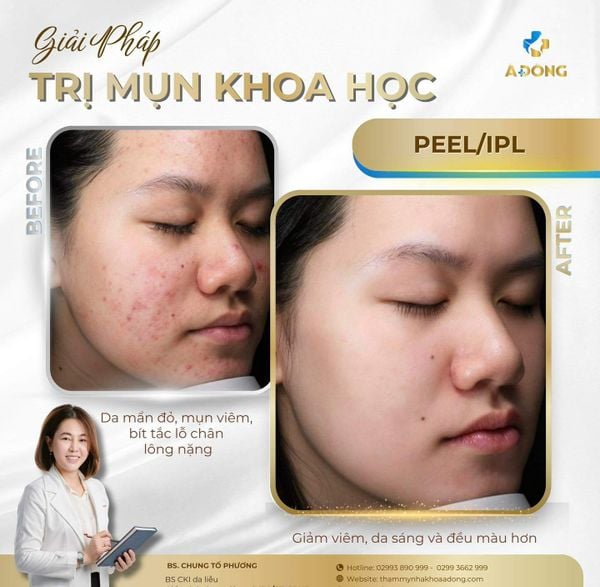

Thực tế, mụn không chỉ là vấn đề trên bề mặt da, mà là sự mất cân bằng của tuyến bã nhờn, vi khuẩn và hàng rào bảo vệ da.

Nếu không được chẩn đoán đúng nguyên nhân, điều trị sai cách dễ khiến da tổn thương, để lại thâm – sẹo – và rối loạn sắc tố lâu dài.

Mỗi khách hàng mụn đều được Bác sĩ CK1. Chung Tố Phương trực tiếp soi da bằng thiết bị chuyên sâu,

Xác định chính xác nguyên nhân – loại mụn – mức độ viêm

Lập phác đồ điều trị cá nhân hoá, kết hợp công nghệ y khoa và liệu trình phục hồi

Theo dõi sát tiến trình điều trị, điều chỉnh kịp thời giúp da cải thiện an toàn – bền vững.

Kết quả: da sạch mụn, mịn khỏe – không kích ứng, không bong tróc, không để lại vết thâm sau liệu trình.